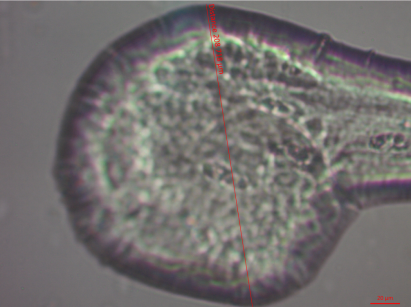

TEM analysis

To ensure the formation of novasome vesicles, we conducted TEM imaging on N1. fig. 2 shows that the novasomes obtained from N1 appeared to be non-aggregating oligolamellar nanovesicles with spherical shape and narrow size distribution. The fig. clearly indicates that the diameter of the vesicles was in the nano-range and consistent with PS measurement.

Fig. 2: TEM Image of N1 formula in magnitude a. 38000 b. 71000 and c. 97000 (Area with two different colors of arrow show different lamellar of bilayer)